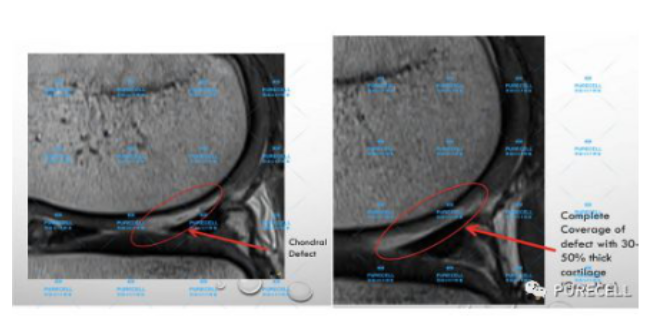

PURECELL首席科學家以及運動醫療專家已經驗證了UCF對膝關節修復的有效性,下圖是UCF軟骨及半月板修復前後影像對比。

UCF膝關節修復的主要原理是通過UCF成分,改善膝關節內環境,有效激活幹細胞靶向修復膝關節組織,修復韌帶損傷、半月板損傷,修復軟骨及髕骨等組織,能有效減少軟骨受損、骨刺等所帶來的疼痛,並且有效避免了軟骨半月板等膝關節組織的持續磨損和惡化,從根源上改善膝關節疼痛等問題給生活帶來的困擾。